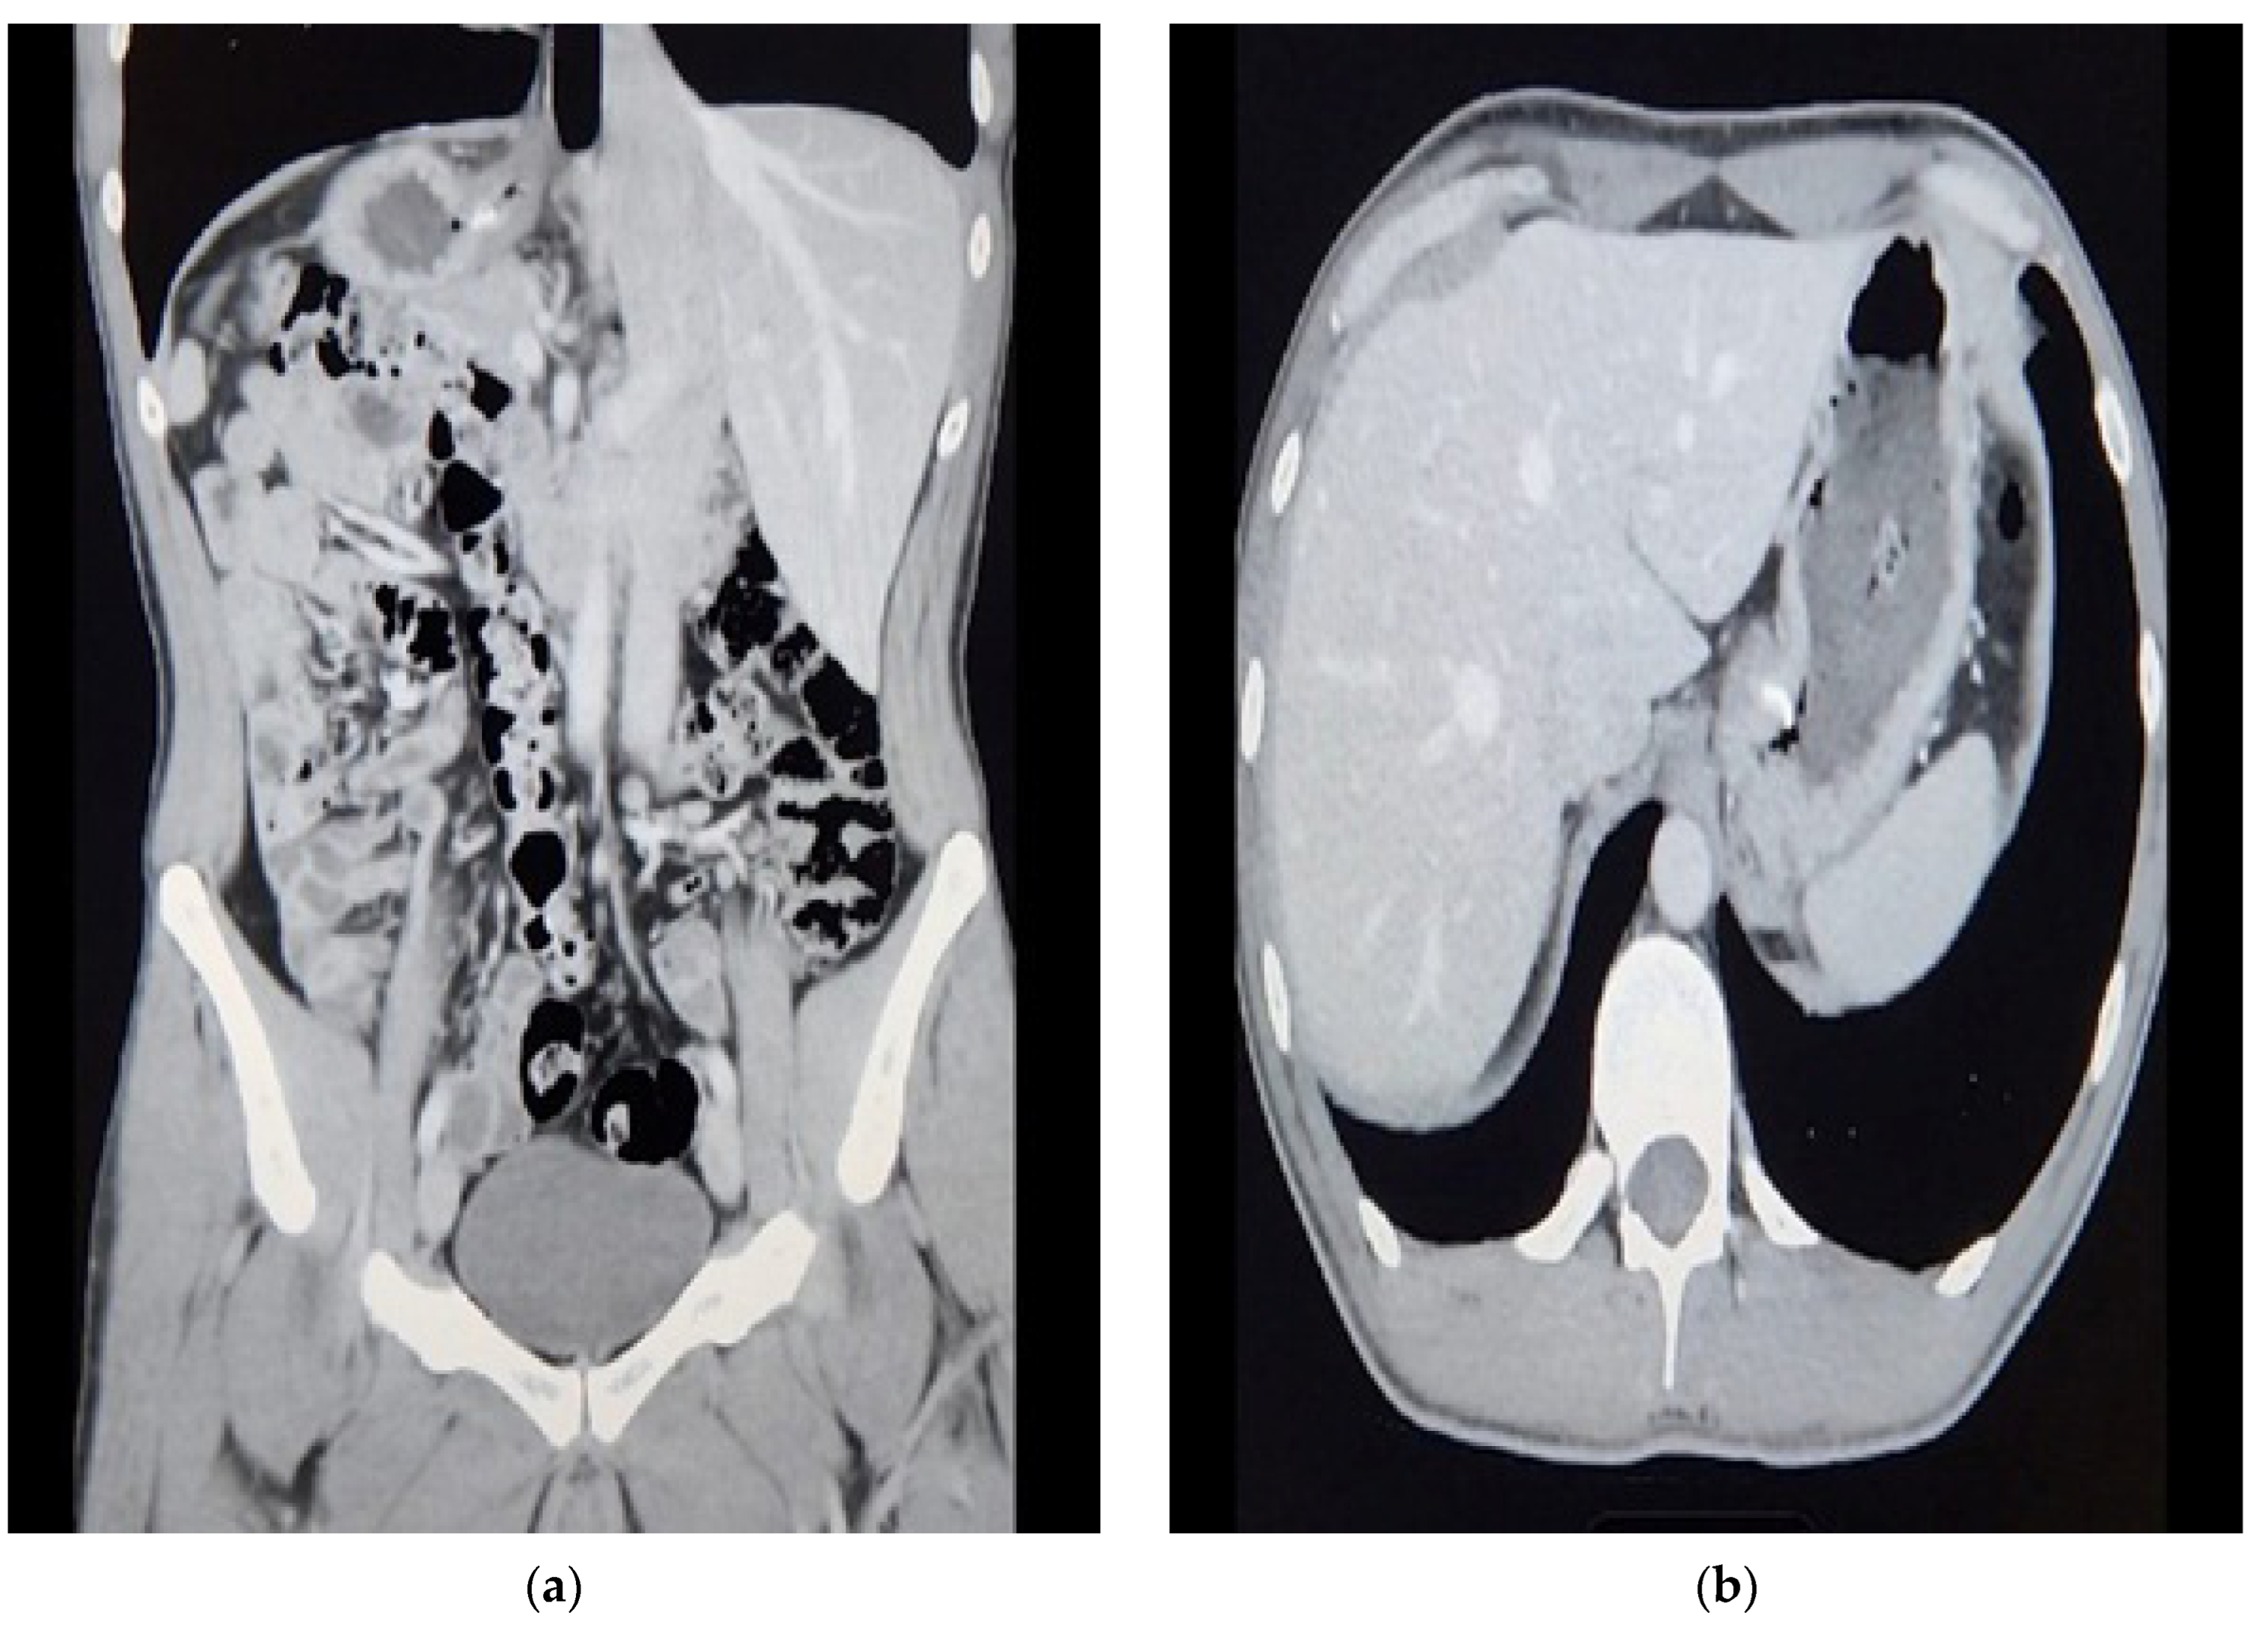

This is a case of a 31-year-old male patient from Saudi Arabia who was otherwise medically free and presented with status post-endoscopic fundoplication that was performed in another country 3 years ago. The patient reported that he developed a post-operative hemothorax that was managed immediately with a right thoracotomy and chest tube. He came to the clinic with a complaint of severe gastroesophageal reflux. As per the patient, it was worse than the first operation. We referred him to a gastroenterologist for his opinion, and he believed the first operation failure could predict the second trial failure, so a surgical approach was preferable. He had a follow-up upper GI endoscopy performed at another hospital, of which no report is available to us. A CT scan was performed with both oral and IV contrast in one of the hospitals; images reviewed in our hospital showed no chest pathology, yet the abdomen showed a hiatal hernia and stomach thickening, describing the ancient fundoplication folds (Figure 1). Esophagogastroduodenoscopy (EGD) was carried out, and it revealed normal findings.

Figure 1. CT scan of the abdomen pelvis: (a) Coronal; (b) Transverse. Suspicious increased wall thickening of the proximal stomach extending to the gastroesophageal junction.